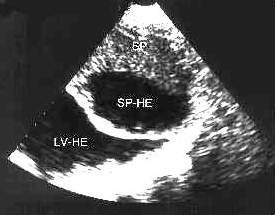

2.腹部超聲檢查 當脾臟損傷時可顯示脾輪廓不整齊,影像中斷,疑有包膜下血腫,並可見脾臟進行性腫大和雙重輪廓影像,同時可顯示腹腔內100ml 以上的積液。脾包膜斷裂時,可見脾臟表面欠光滑整齊,連續性中斷,可探及條索狀暗帶,脾實質回聲尚均勻,脾周及左右髂窩內可探及不等量的液性暗區。當包膜、脾實質同時斷裂時,可見脾臟包膜斷裂,脾實質內可探及一處或多處不規則低回聲區,脾周、肝前、肝腎之間、左右髂窩可探及大量液性暗區。遲發性脾臟破裂時,需多次超聲檢查才能發現實質破裂。